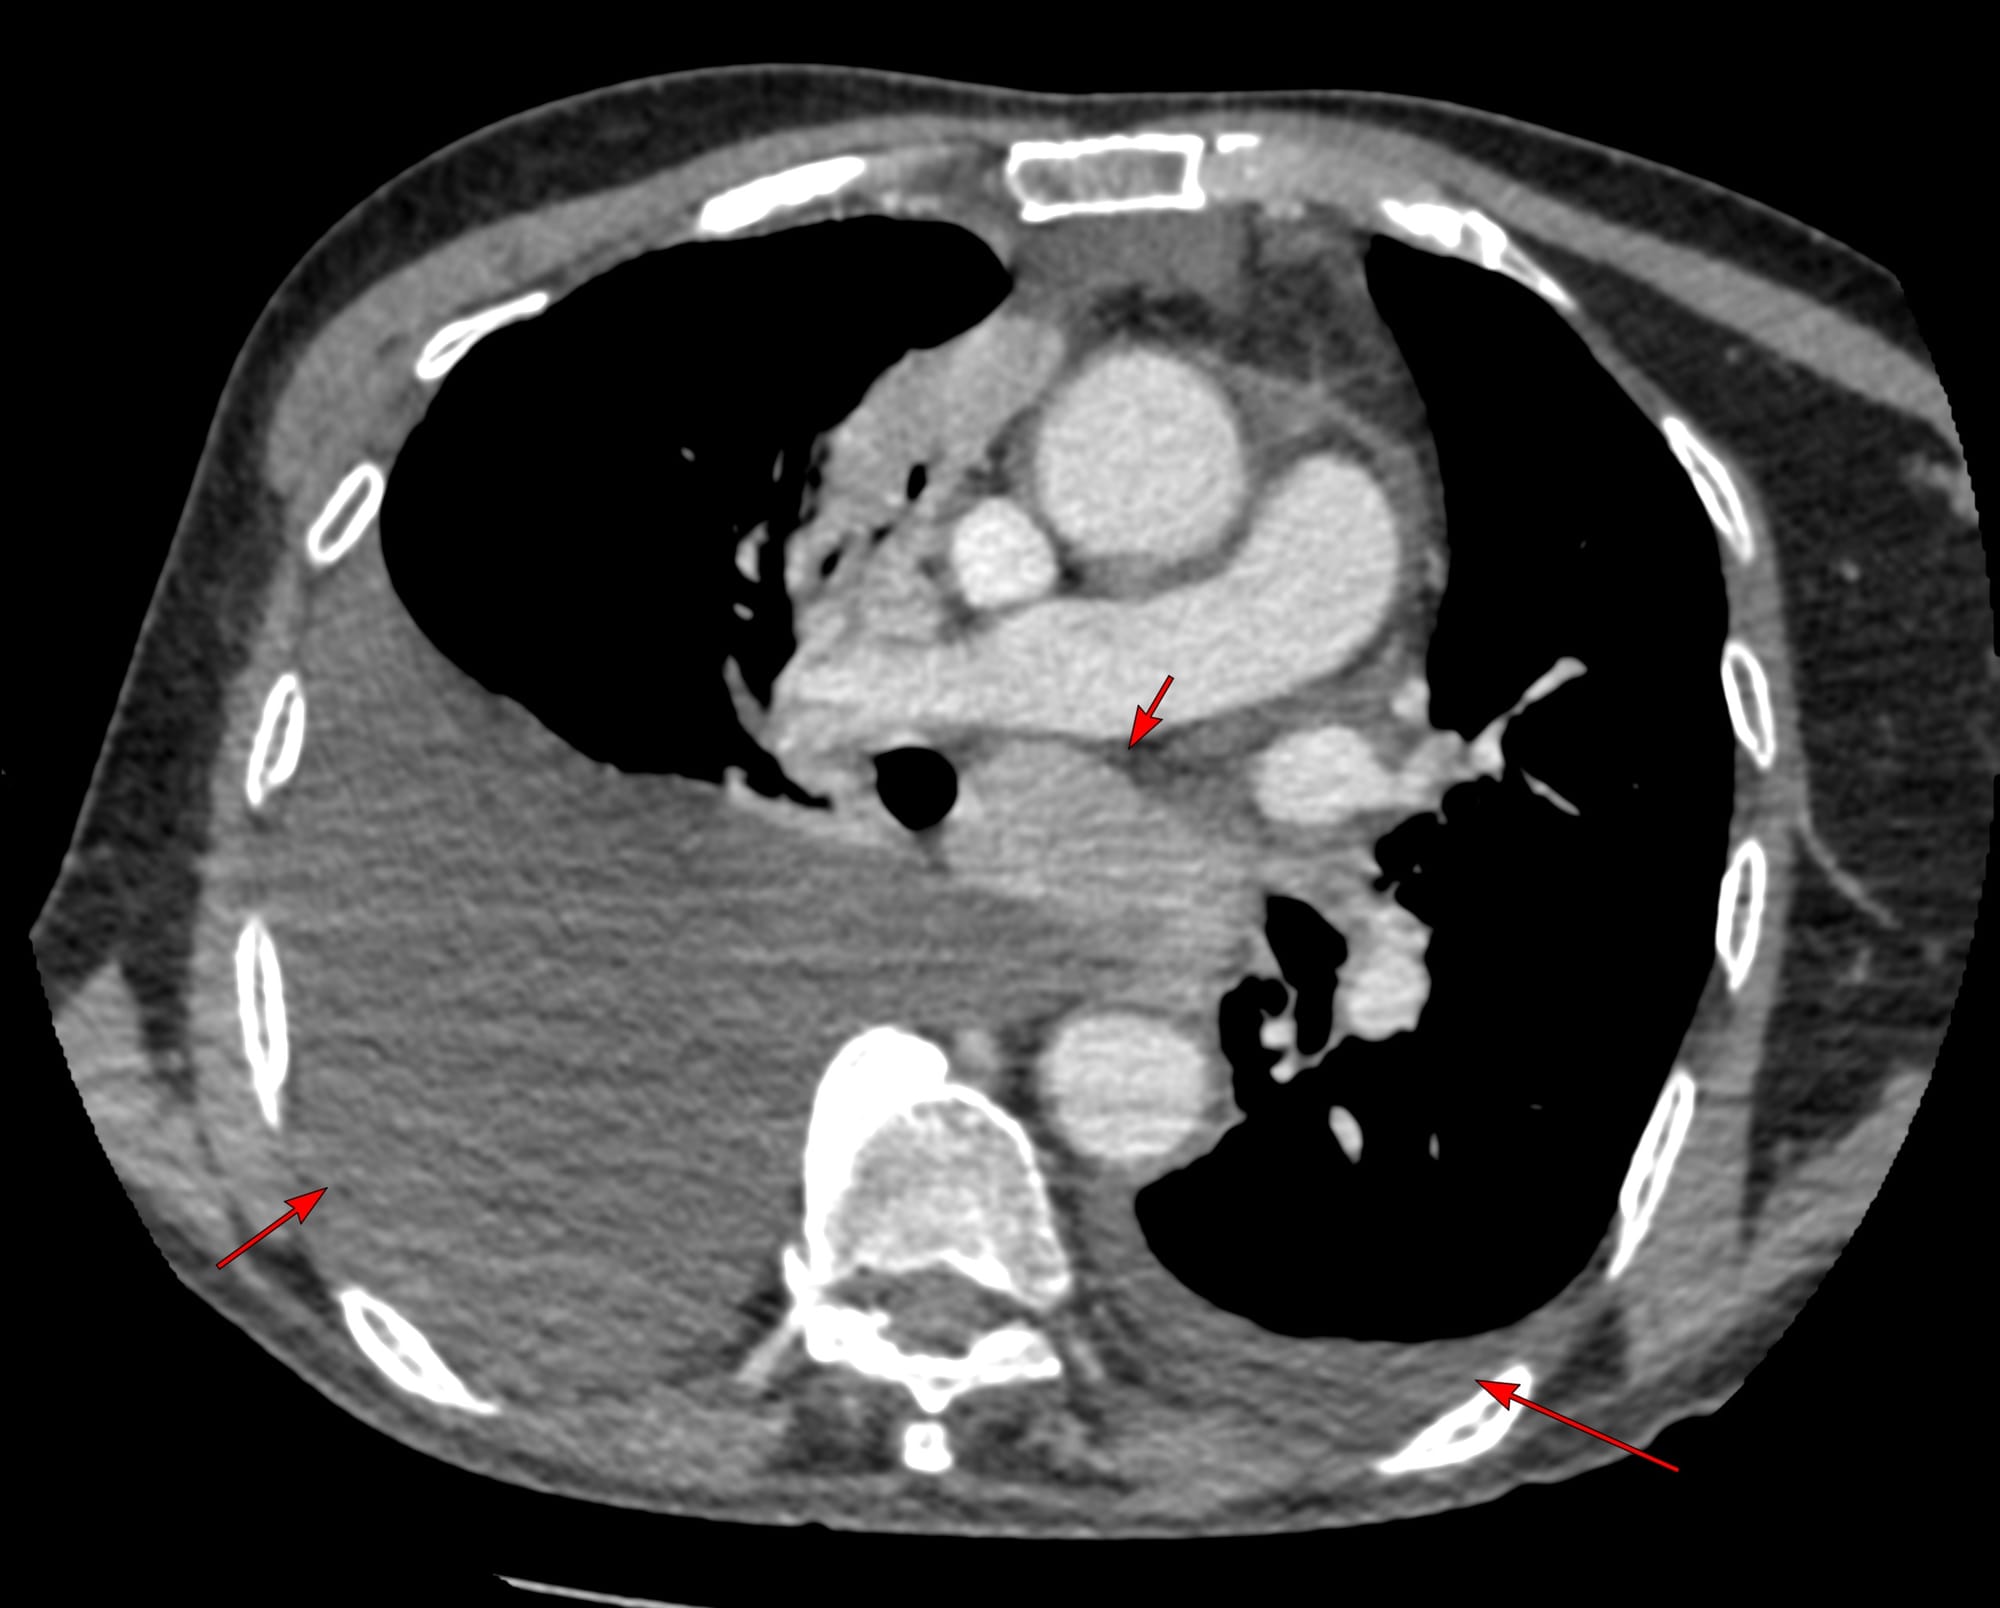

3 months later, he clinically worsened and CT scan showed the same nodes with mild increase in the subcarinal node size and bilateral effusions and he was referred for a CT guided biopsy of the subcarinal node. The short axis of the node was 25 mm, so biopsy was feasible.

The effusion was a concern, but in the prone position, the fluid moved anteriorly and did not come in the way, though a transeffusion or transpneumothorax biopsy is always a possibility.

The lung was almost at the midline and there was concern that a transparenchymal approach (A) may be needed as in the last case.

Findings: Enlarged mediastinal nodes

Lesion Biopsied: Subcarinal node

Size of Lesion: 25.1 mm z axis